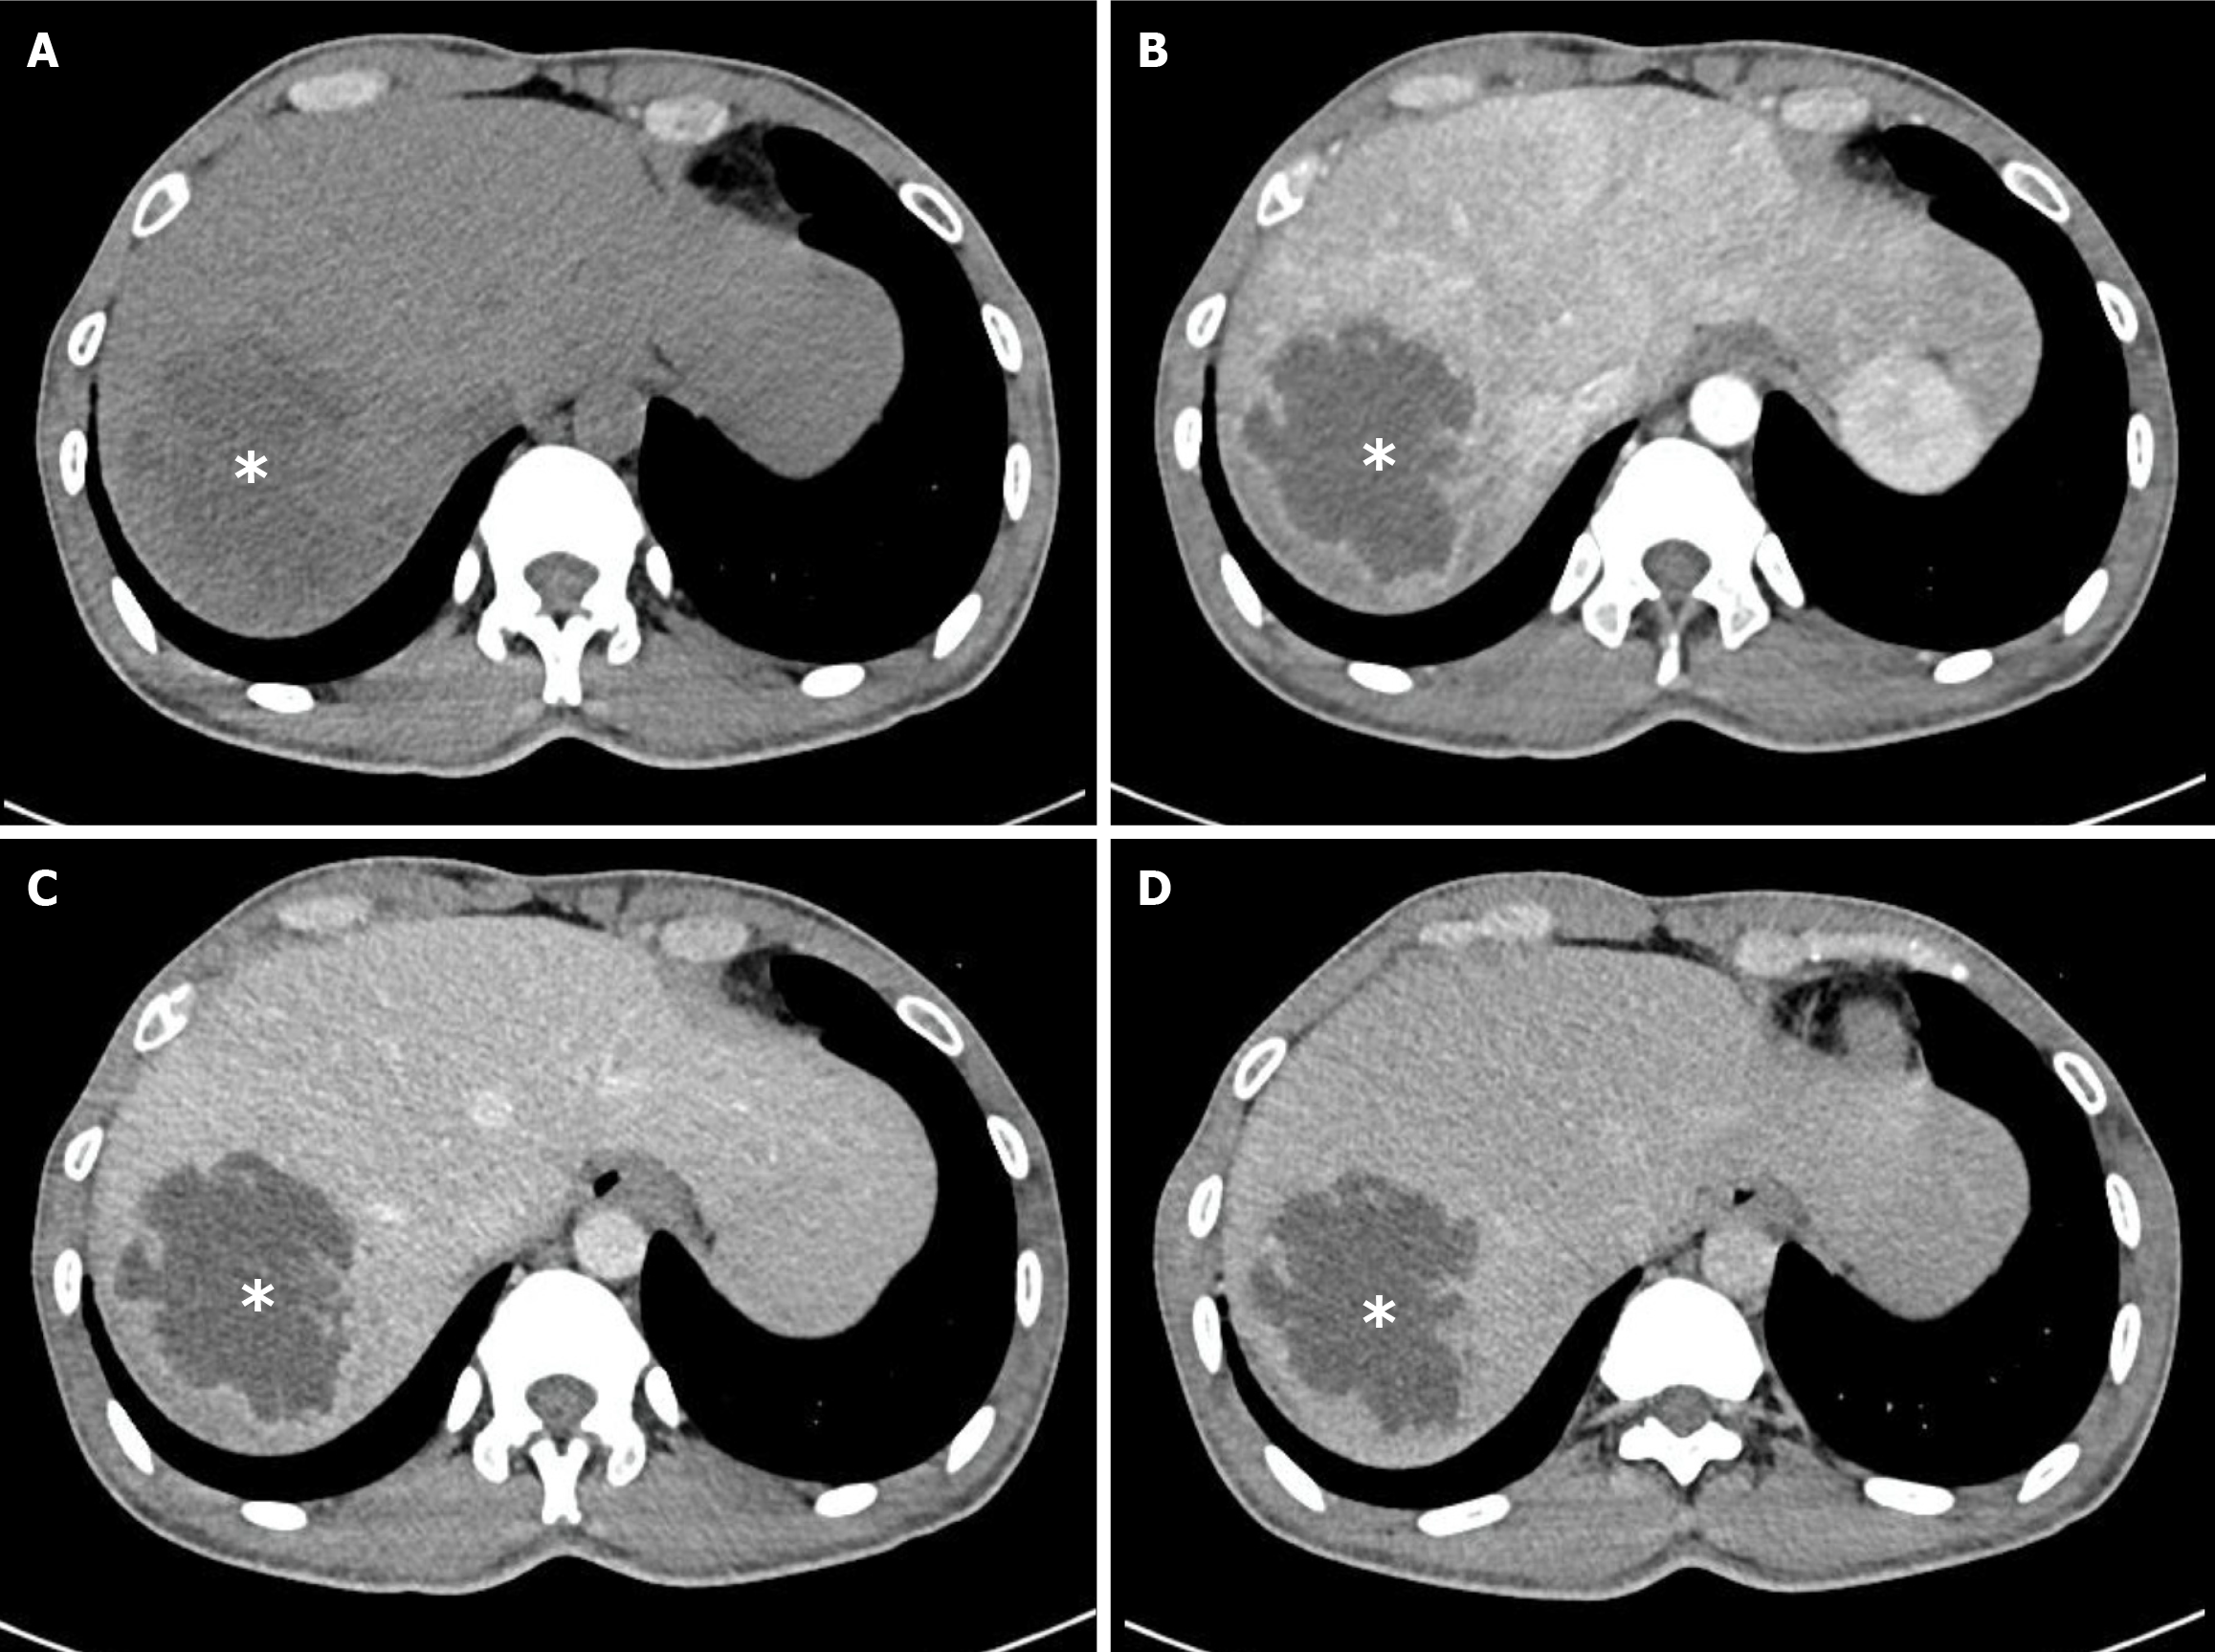

Figure 3 Characteristics of Klebsiella pneumoniae liver abscess on multislice computed tomography scan.

The abscesses (white asterisk) appear as multiple lesions with irregular and lobulated margins. The internal architecture of the abscesses is heterogeneous, reflecting varying degrees of necrosis, fluid content, and inflammatory debris. A: Non-contrast phase; B: Arterial phase; C: Portal venous phase; D: Delayed phase.